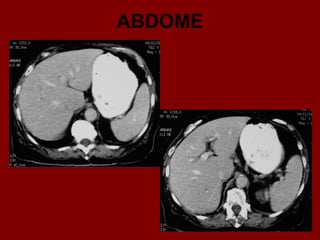

ABDOME